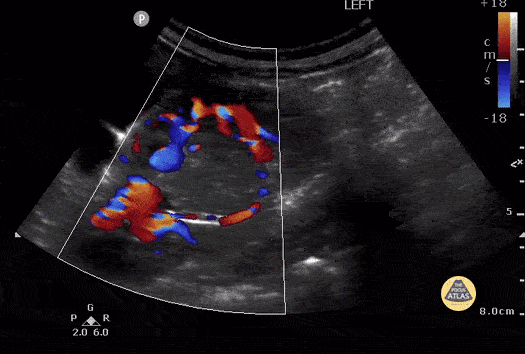

Incidental finding of a Wilm's tumor in 3 yo female presenting to the PED with fever and lower abdominal pain. Educational scan that turned out to significantly alter management. Pt had right nephrectomy of localized tumor. Case Series 2 of 2 Contributor: Melinda Tonelli MD, University of Rochester, Rochester NY